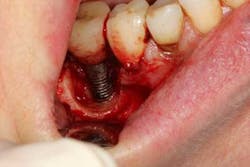

Fig. 5